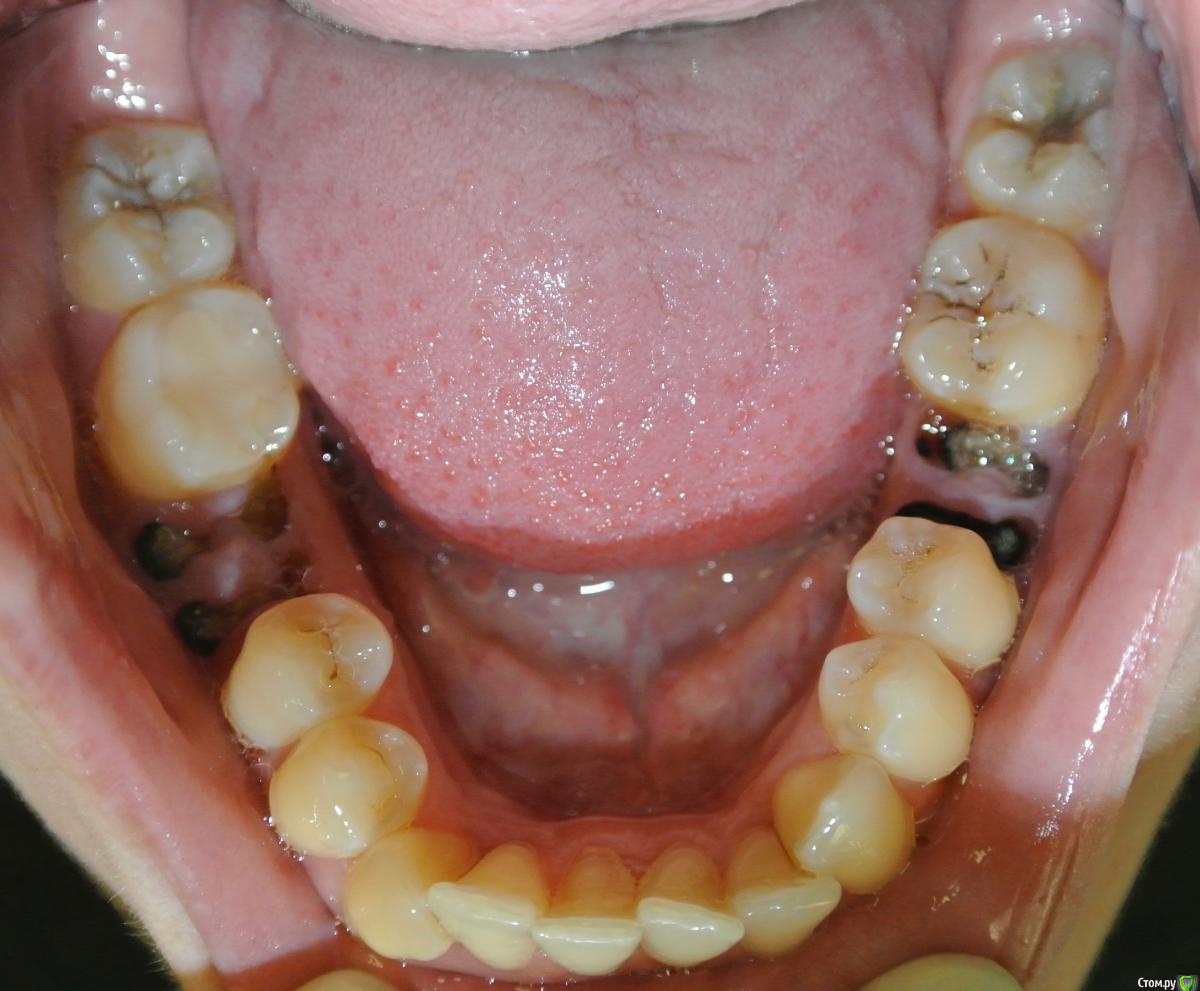

an_ver Опубликовано 4 апреля, 2015 Поделиться Опубликовано 4 апреля, 2015 Пипец! С таким гнильем на н\ч девочка думает о средней линии.. 3 Ссылка на комментарий

229KAMA Опубликовано 11 апреля, 2015 Поделиться Опубликовано 11 апреля, 2015 Пациентка Н., 30 лет. Жалоба на смещение средней линии верхнего зубного ряда. Из анамнеза: зуб 1.3. удален в возрасте 9 лет (ох уж эти удаляльщики). Как можно скорректировать положение средней линии?DSC_7521.JPGDSC_7522.JPGDSC_7524.JPGDSC_7525.JPGDSC_7526обр.jpgDSC_7527 обр.jpgСкажите пожалуста Я вот прочитал "1.3. удален в возрасте 9 лет" -это постоянный клык вроде так по номеру и квадранту (постоянный). А на фото Я вижу его на предоставленных фотографиях , что он стоит в челюсти. Или Я вижу , что то не так. Если ошибаюсь то возможно по не опытности ? приношу свои извинения. Ссылка на комментарий